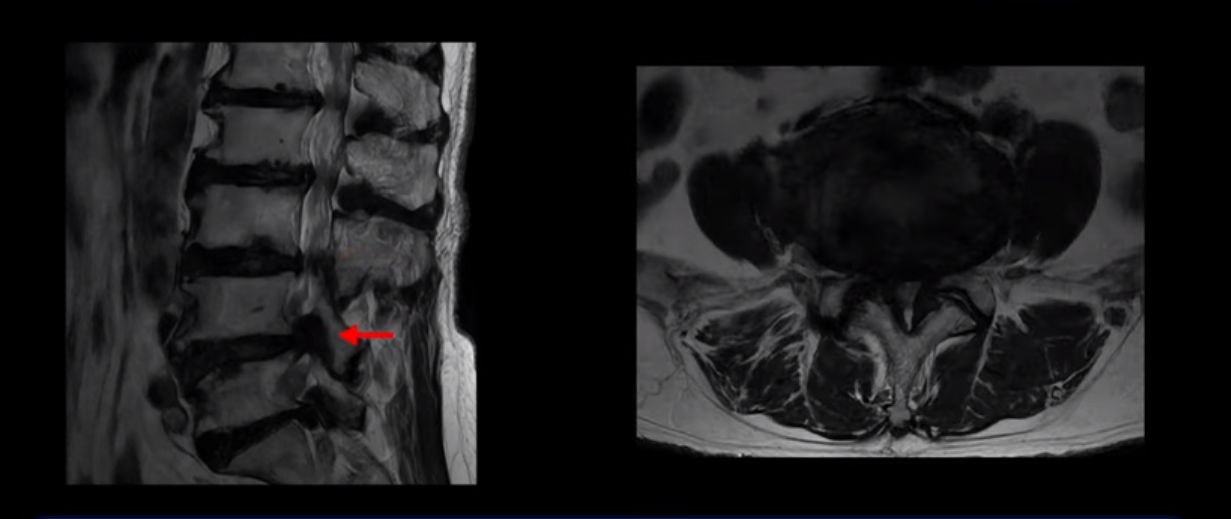

이 환자분은 MRI로 보면 허리 여러 마디가 신경이 매우 심하게 눌려 보이는 분입니다. 이분 MRI를 보면서 간단히 설명해 드린 후 어떻게 이렇게 신경이 심하게 눌린 환자분이 수술 없이 근육신경재활치료로 좋아질 수 있는지, 다리가 아파 걷지 못하는 환자가 어떻게 안 아프고 잘 걸을 수 있게 되는지, 10년 동안 괴로웠던 양 발의 시린 증상은 어떻게 사라질 수 있는지, 치료는 어떻게 하는지 자세히 설명 드리겠습니다.

MRI 보시면 (2-8) 허리의 5마디가 전부 다 심하게 퇴행되어 있습니다.

5마디 전부 다 심한 중심성 협착이 있습니다.

이렇게 모두 다 심하게 막히는 경우는 드문데요. 또한 오른쪽, 왼쪽 신경이 빠져나가는 추간공도 다 심하게 막혀있습니다.

오른쪽, 왼쪽 이렇게 신경 구멍들이 다 좁아지고 신경이 눌리니까 양쪽 다리가 발바닥까지 아파서 걷기 어렵고 양쪽 발이 10년 넘게 시린 겁니다. 당연히 수술해서 눌린 신경을 풀어줘야 한다고 들으셨는데요. 이런 환자분을 어떻게 수술 없이 치료할까요? 지금부터 설명해 드립니다.